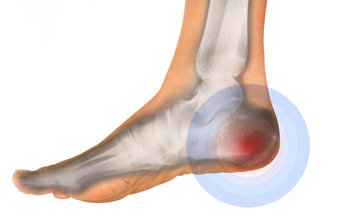

Plantar Fasciitis

One of the main causes of heel pain is a condition known as plantar fasciitis. The plantar fascia is a band of tissue that extends along the bottom of the foot, from the toe to the bottom of the heel. A rip or tear in this ligament can cause inflammation of these tissues, resulting in heel pain. People who do not wear proper fitting shoes are often at risk of developing problems such as plantar fasciitis. Unnecessary stress from ill-fitting shoes, weight change, excessive running, and wearing non-supportive shoes on hard surfaces are all causes of plantar fasciitis.

Heel Spur

A third cause of heel pain is a heel spur. A heel spur occurs when the tissues of the plantar fascia undergo a great deal of stress, leading to a separation of the ligament from the heel bone entirely. This results in a pointed fragment of bone on the ball of the foot, known as a heel spur.